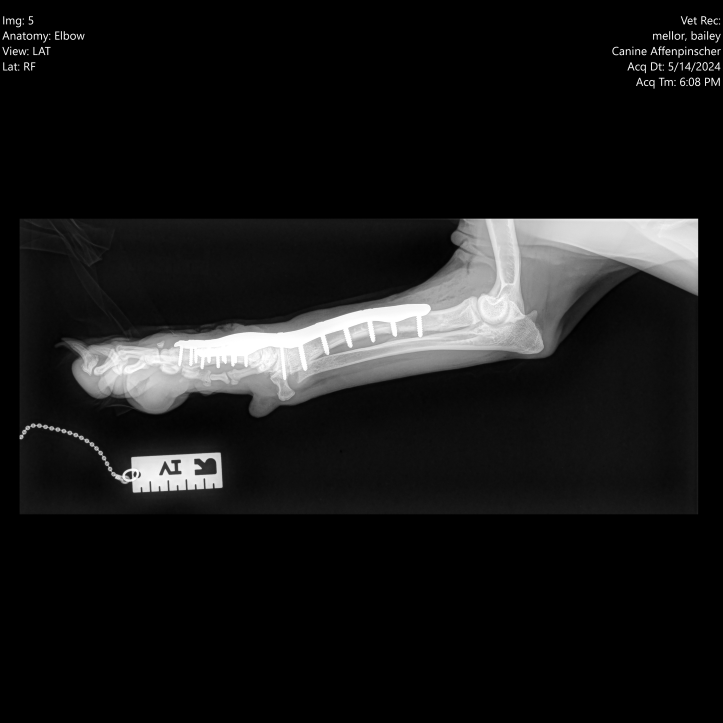

In 2023, Bailey was admitted to Dovecote Veterinary Hospital, where Orthopaedic Specialist James Pratt performed a combined angle correction and partial carpal arthrodesis (PCA) to address the deformity and the resulting arthritis. This advanced surgical procedure involved the use of cutting-edge technology to ensure precision and effectiveness.

James, along with a highly trained surgical team, employed 3D-printed guides made by Bill Oxley at Vet3D to make precise cuts in the correct direction. These guides were tailored specifically for Bailey's unique anatomical structure, ensuring optimal accuracy. Following the bone cuts, a custom 3D-printed plate was used to align the bones correctly while the carpal joints fused. This approach not only facilitated the proper alignment of Bailey's carpus, but also promoted successful joint fusion, ultimately relieving the pain associated with osteoarthritis.